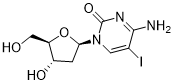

馬鞍山致研生物醫(yī)藥科技有限公司成立于馬鞍山市鄭浦港新區(qū)現(xiàn)代產(chǎn)業(yè)園。公司專(zhuān)注于生物小分子、醫(yī)藥中間體相關(guān)產(chǎn)品的研發(fā)和生產(chǎn),產(chǎn)品主要包括DNA亞磷酰胺單體、RNA亞磷酰胺單體、特殊單體以及按照客戶(hù)要求定制的RNA和DNA,并且公司提供定制合成等方面的研究服...

馬鞍山致研生物醫(yī)藥科技有限公司成立于馬鞍山市鄭浦港新區(qū)現(xiàn)代產(chǎn)業(yè)園。公司專(zhuān)注于生物小分子、醫(yī)藥中間體相關(guān)產(chǎn)品的研發(fā)和生產(chǎn),產(chǎn)品主要包括DNA亞磷酰胺單體、RNA亞磷酰胺單體、特殊單體以及按照客戶(hù)要求定制的RNA和DNA,并且公司提供定制合成等方面的研究服...